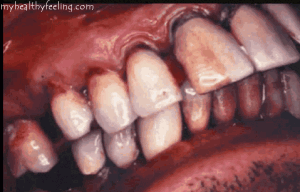

Rotten teeth pictures

Here are pictures of rotten teeth, you can make out the areas that are affected due to various causes that come into play